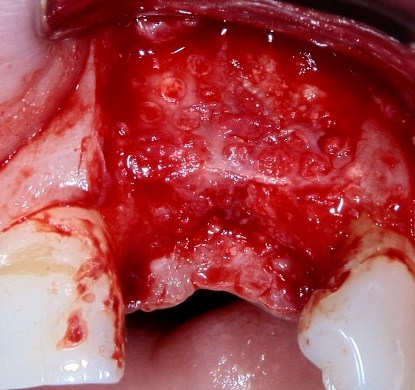

Например, в следующей ситуации:

Оставить так, как есть — это значит, сильно рисковать имплантом и объемом альвеолярного гребня — фактически, большая часть импланта пятого зуба «висит в воздухе». Поэтому получившуюся костную полость мы заполняем аутокостной стружкой в смеси с Bioss и закрываем коллагеновой мембраной BioGide:

Другой вариант. Имплантируем, но существующего объема костной ткани недостаточно для получения адекватного эстетического и функционального результата:

Поэтому мы используем мембрану Geistlich BioGide и всё ту же аутокостную стружку: